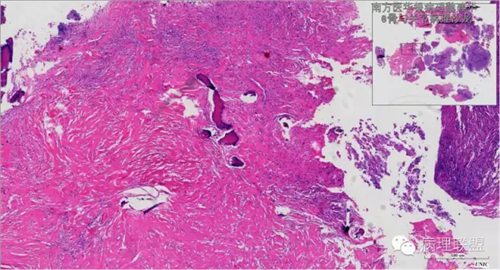

来源于组织细胞的相似性骨病ECD vs RDD 看图说话

病例由南方医华银病理魏建华提供,致谢。